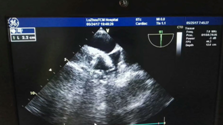

近日, 我院專家團隊通力配合,成功為一名78歲高齡的患者實施了左心耳封堵術(shù)。專家在患者左心耳置入了一個封堵器,從而有效地預(yù)防了患者發(fā)生房顫卒中的風險,據(jù)悉,這是川南地區(qū)成功開展的首例經(jīng)食道超聲指引下的“左心耳封堵術(shù)”。????? ?手術(shù)中?78歲高齡老人房顫致血栓???服藥無效??? ?? 江陽區(qū)一...